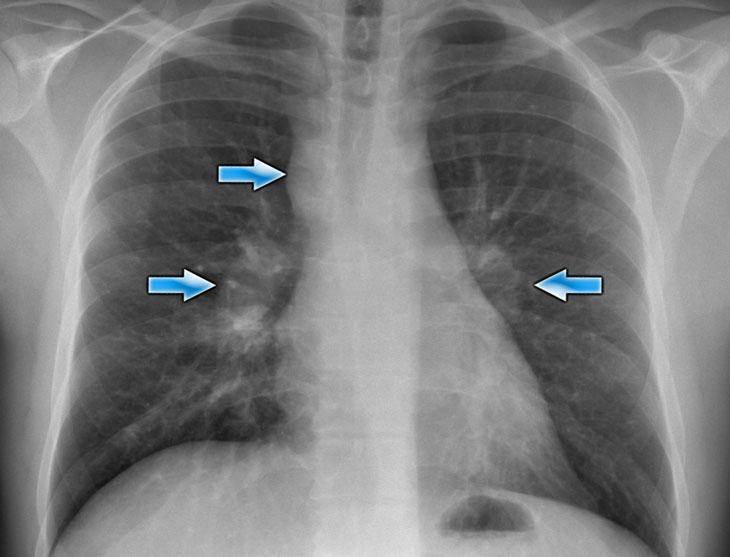

To rốn phổi

Bảng tóm tắt các nguyên nhân gây to rốn phổi.

Rốn phổi bình thường:

- Vị trí bình thường – rốn trái cao hơn rốn phải

- Tỷ trọng đồng đều hai bên

- Hình thái phân nhánh mạch máu bình thường

To rốn phổi thường do hạch bạch huyết to hoặc mạch máu giãn to.

To rốn phổi – ca 1

Trong trường hợp này, bóng rốn phổi to ra ở cả hai bên. Nguyên nhân có thể do mạch máu giãn to hoặc hạch bạch huyết to. Một dấu hiệu rất có giá trị trong trường hợp này là khối nằm bên phải khí quản.

Đây được gọi là dấu hiệu 1-2-3 trong bệnh sarcoidosis, tức là to rốn phổi trái, rốn phổi phải và hạch cạnh khí quản.

Dưới đây là thêm một số ví dụ về bệnh sarcoidosis.

Nhấp vào hình để phóng to.

- Hạch bạch huyết to và hình ảnh kính mờ (ground-glass) ở phổi

- Hạch bạch huyết to, dấu hiệu 1-2-3

- Hạch bạch huyết to khối lớn

- Dấu hiệu 1-2-3

- Hình ảnh nốt ở phổi, không có hạch bạch huyết to

- Hạch bạch huyết rốn phổi và cạnh khí quản to